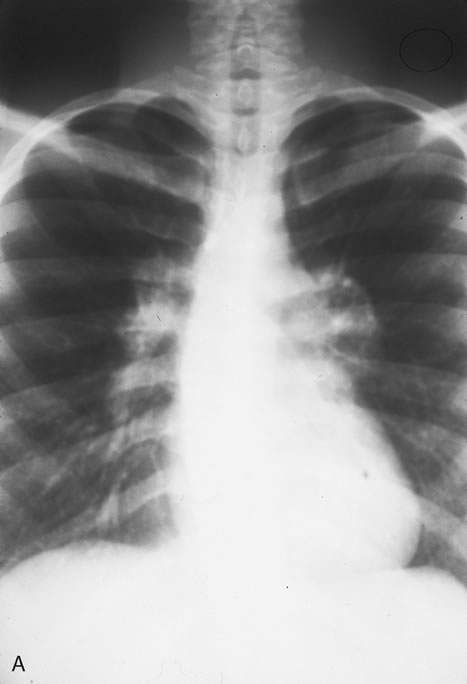

In the immunocompromised, especially organ transplant recipients and patients with AIDS, CMV commonly is responsible for serious clinical syndromes. It causes an interstitial pneumonia, resulting in dyspnea and dry cough, with interstitial infiltrates on the roentgenogram. Subacute encephalitis, enterocolitis, adrenalitis, and adrenal necrosis may be noted.

Pneumocystis carinii pneumonia once was the most common presentation of AIDS. It is typically of insidious onset, with features including dry cough, dyspnea, and a diffuse bilateral interstitial infiltrate evident on a chest roentgenogram. Typical multifocal fundus lesions have been described. They are yellow-white and have a characteristic pattern on fluorescein angiography (Fig. 10A, 10B, and 10C). Diagnosis is made by demonstrating the protozoon via sputum induction, bronchioalveolar lavage, and transbronchial or open-lung biopsies. Treatment modalities include trimethoprim-sulfamethoxazole (TMP-SMX).31